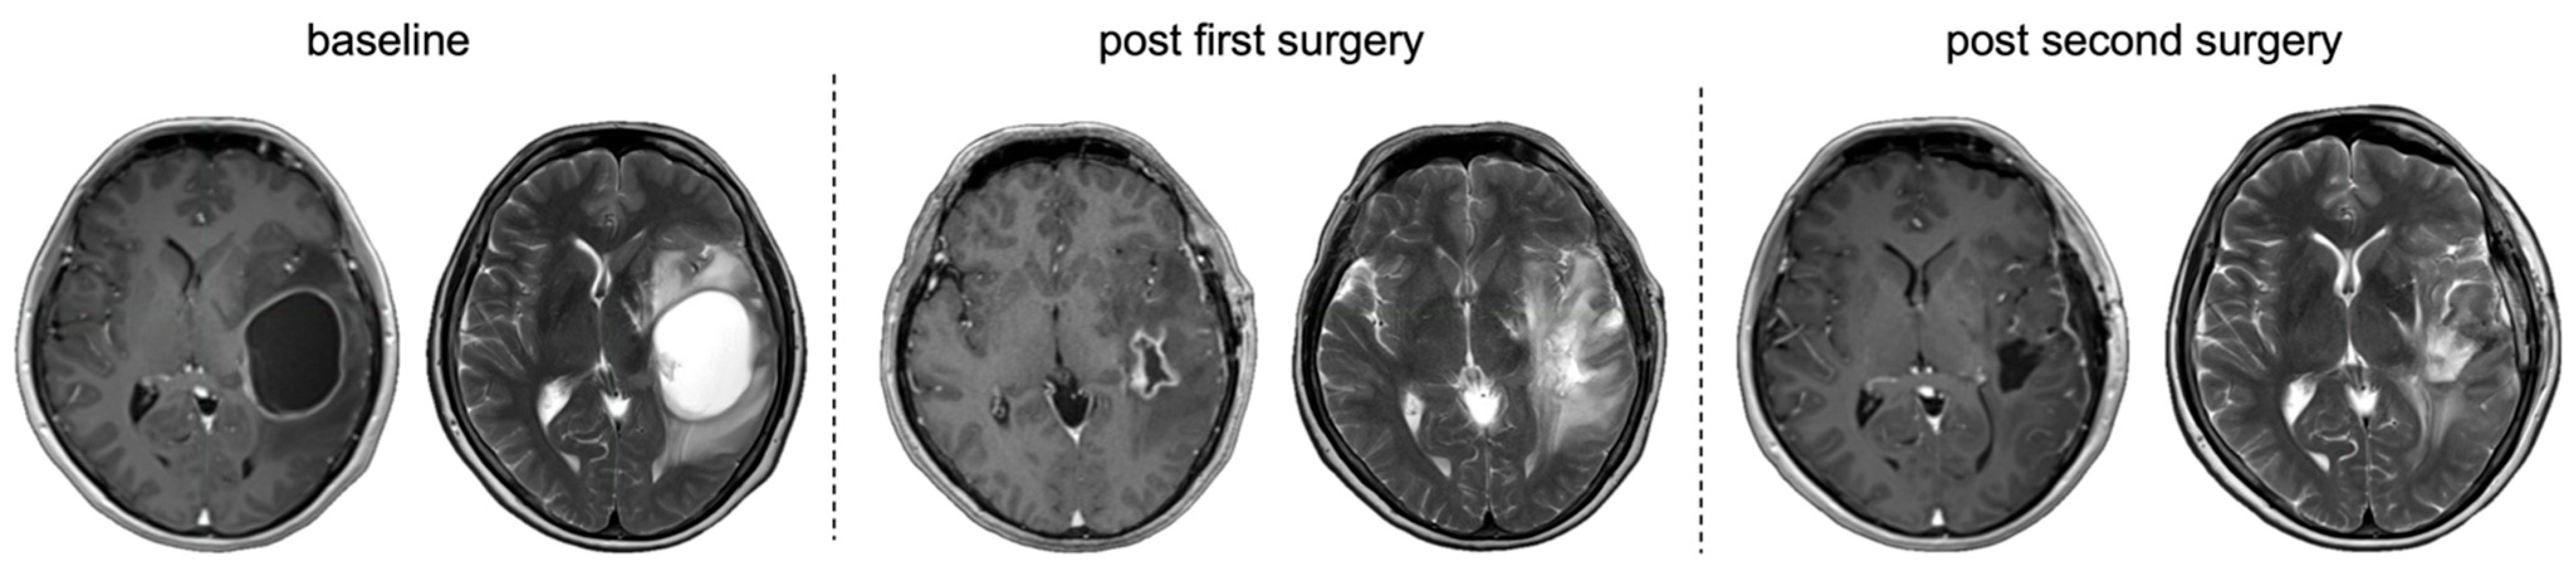

3.5.3. Primary Debulking